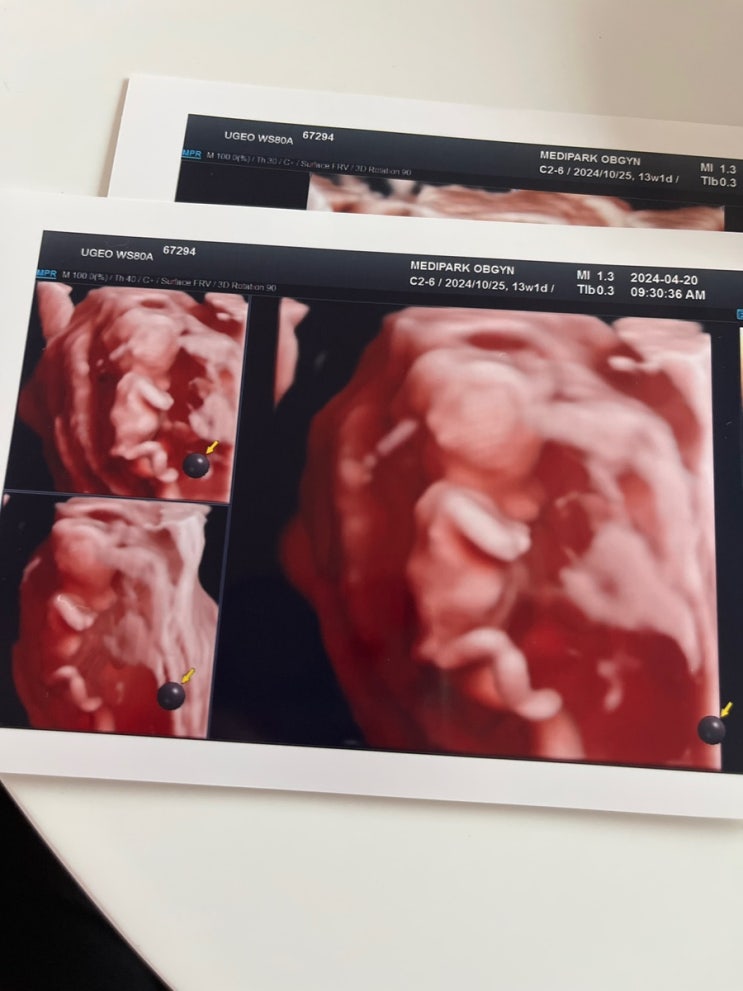

임신 13주차 - 16주차|목 투명대 검사, 한화 교향악 축제, 힙합플레야 페스티벌

임신일기 13주차 - 16주차 코 뼈, 목 투명대 검사 한화 교향악축제 서울시립교향악단 힙합플레야 페스티벌 ...